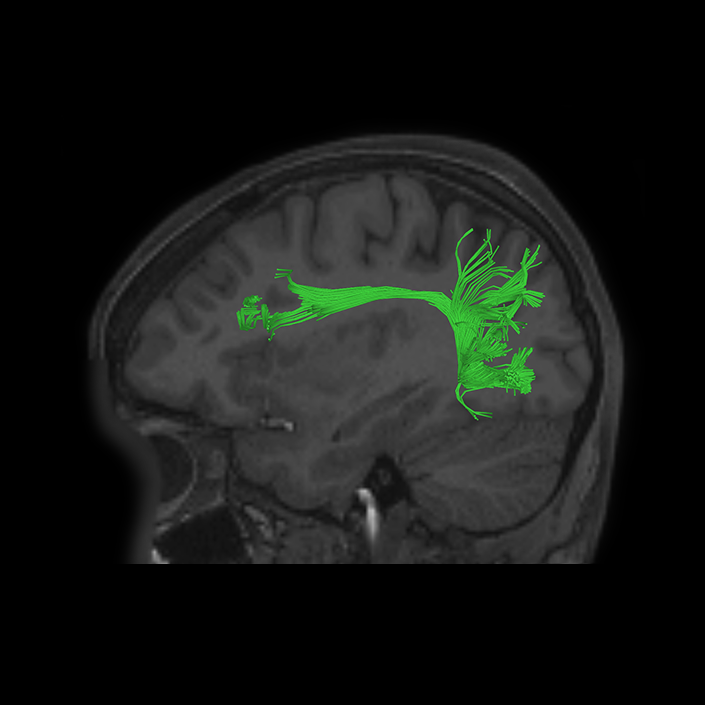

ᐅ SummaryArea 44: part of the inferior frontal gyrus of the lateral frontal lobe. Translates abstract and intentional information in the prefrontal cortex to more detailed representations to help guide the production of verbal and manual actions. In addition to its known association with Broca's area, is sometimes represented as part of Broca's complex ᐅ Where is it?Area 44 is at the posterior most part of the inferior frontal gyrus. It is the anterior bank of pars opercularis of the IFG. ᐅ What are its borders?Area 44 borders area 45 anteriorly and area 6r posteriorly. Area 8C is its medial border and its inferior border is wedged between then upper borders of Areas 6R and 6V. Its superior edge borders IFSp and IFJa. Its opercular surface is FOP4. ᐅ What are its functional connections?Area 44 demonstrates functional connectivity to areas SFL, IFSp, IFJa, 45, 47s, 47L, 9a, 9m, 8AV, 8BL and 8C in the dorsolateral frontal lobe, area 8BM in the medial frontal lobe, area 55b in the premotor areas, areas FOP5, AVI and PSL in the insula- opercular region, areas TGd, STSdp and STSvp in the temporal lobe, areas PFm, and PGi in the inferior parietal lobe, and no areas in the medial parietal lobe. ᐅ What are its white matter connections?Area 44 is structurally connected to the arcuate/SLF and the FAT. Connections with the arcuate/SLF project posteriorly and wrap around the Sylvian fissure to the middle temporal gyrus to end at TE1a and TE1m. There are also projections from the arcuate/SLF before it terminates to parcellations A5 and STSdp. The majority of the inferior connections of the frontal aslant tract end at 44, the tract is connected superiorly to superior frontal gyrus parcellations SFL, 6ma and s6-8. Local short association bundles are connected with 45 and 8C. White matter tracts from 44 in the right hemisphere have less consistent connections with the arcuate/SLF. ᐅ What is known about its function?Area 44 translates abstract and intentional information in the prefrontal cortex to more detailed representations to help guide the production of verbal and manual actions. Area 44, in addition to its known association with Broca's area, is sometimes represented as part of "Broca's complex", including Brodmann Areas 45, 46, 47 and the mesial supplementary motor area of 6, which contribute to a frontal-subcortical circuit. The right pars opercularis has also been implicated in cognitive inhibition in the overall context of working memory. |

DTI image |

ᐅ SummaryArea 45: part of the inferior frontal gyrus of the lateral frontal lobe. In addition to its known association with Broca's area, is sometimes represented as part of Broca's complex ᐅ Where is it?Area 45 is the lateral surface of pars triangularis of the IFG. ᐅ What are its borders?Area 45 borders area 47L anteriorly and area 44 posteriorly. Its superior edge borders area p47r, IFSa, and IFSp. Its opercular surface is conveniently named FOP5 ᐅ What are its functional connections?Area 45 demonstrates functional connectivity to areas SFL, IFSp, 44, a47r, 47s, 47L, 9a, 9p, 9m, 8AV, and 8BL in the dorsolateral frontal lobe, area 8BM in the medial frontal lobe, area 55b in the premotor areas, areas FOP5, and PSL in the insula-opercular region, areas TGd, TGv, TE1a, STSva, STSdp and STSvp in the temporal lobe, area PGi in the inferior parietal lobe, and area 31pd in the medial parietal lobe. ᐅ What are its white matter connections?Area 45 is structurally connected to the arcuate/SLF and IFOF. However, arcuate/SLF connections are not consistent across individuals. Connections with the arcuate/SLF project posteriorly and wrap around the Sylvian fissure to the middle temporal gyrus to end at TE1p. There are also projections from the arcuate/SLF before it terminates to parcellations A4 and PBelt. IFOF connections travel from 45 through the extreme/external capsule and continue posteriorly through the temporal lobe to end at occipital lobe parcellations V1, V2, V3 and V4. Local short association bundles connect with 44 and FOP4. ᐅ What is known about its function?Area 45, in addition to its known association with Broca's area, is sometimes represented as part of "Broca's complex", including Brodmann Areas 45, 46, 47 and the mesial supplementary motor area of 6, which contribute to a frontal-subcortical circuit. |

DTI image |